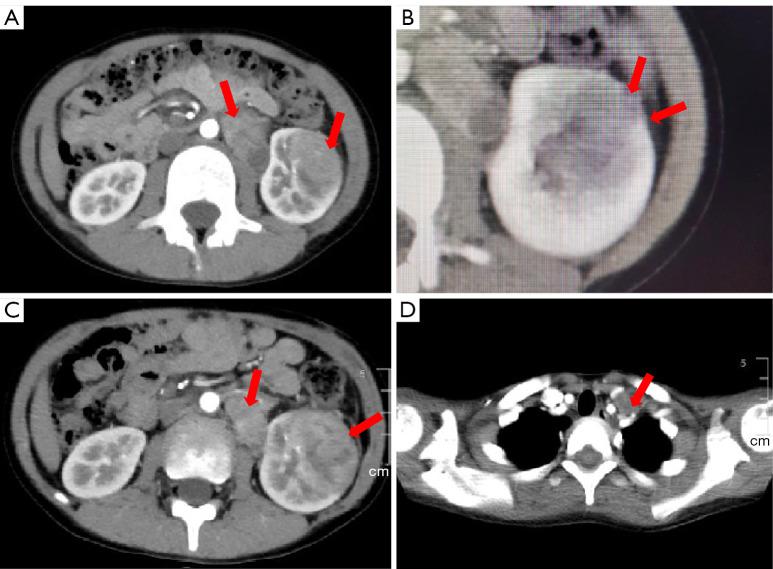

We present the case of an 8-year-old male patient with hematuria and paroxysmal urinary pain. Based on tumor genetic testing results and targeted drug matching analysis, the patient underwent tumor biopsy, tumor radical surgery with vascular osteotomy, and cervicothoracic lymph node dissection. The patient was then treated with a combination of immunotherapy [sintilimab, a drug directed against programmed cell death receptor-1 (PD-1)] and VEGFR tyrosine kinase inhibitor (TKI) (from pazopanib to sunitinib). Throughout the 10 cycles of conventional chemotherapy (seven courses of sintilimab since the start of the third chemotherapy treatment), the patient's condition remained stable, with no tumor recurrence at the primary site. However, in the later stages, the patient developed a large amount of ascites, and the family requested discontinuation of treatment, ultimately leading to the patient's death.

我们报告一例8岁男性血尿及阵发性尿痛患者。根据肿瘤基因检测结果和靶向药物匹配分析,患者接受了肿瘤活检、带血管骨切开的肿瘤根治性手术及颈胸淋巴结清扫。随后患者接受了免疫治疗[信迪利单抗,一种针对程序性细胞死亡受体-1(PD-1)的药物]和VEGFR酪氨酸激酶抑制剂(TKI)(从帕唑帕尼换为舒尼替尼)联合治疗。在整个10周期的传统化疗过程中(自第三次化疗开始共七个疗程的信迪利单抗),患者病情保持稳定,原发部位无肿瘤复发。然而,在后期,患者出现大量腹水,家属要求停止治疗,最终导致患者死亡。